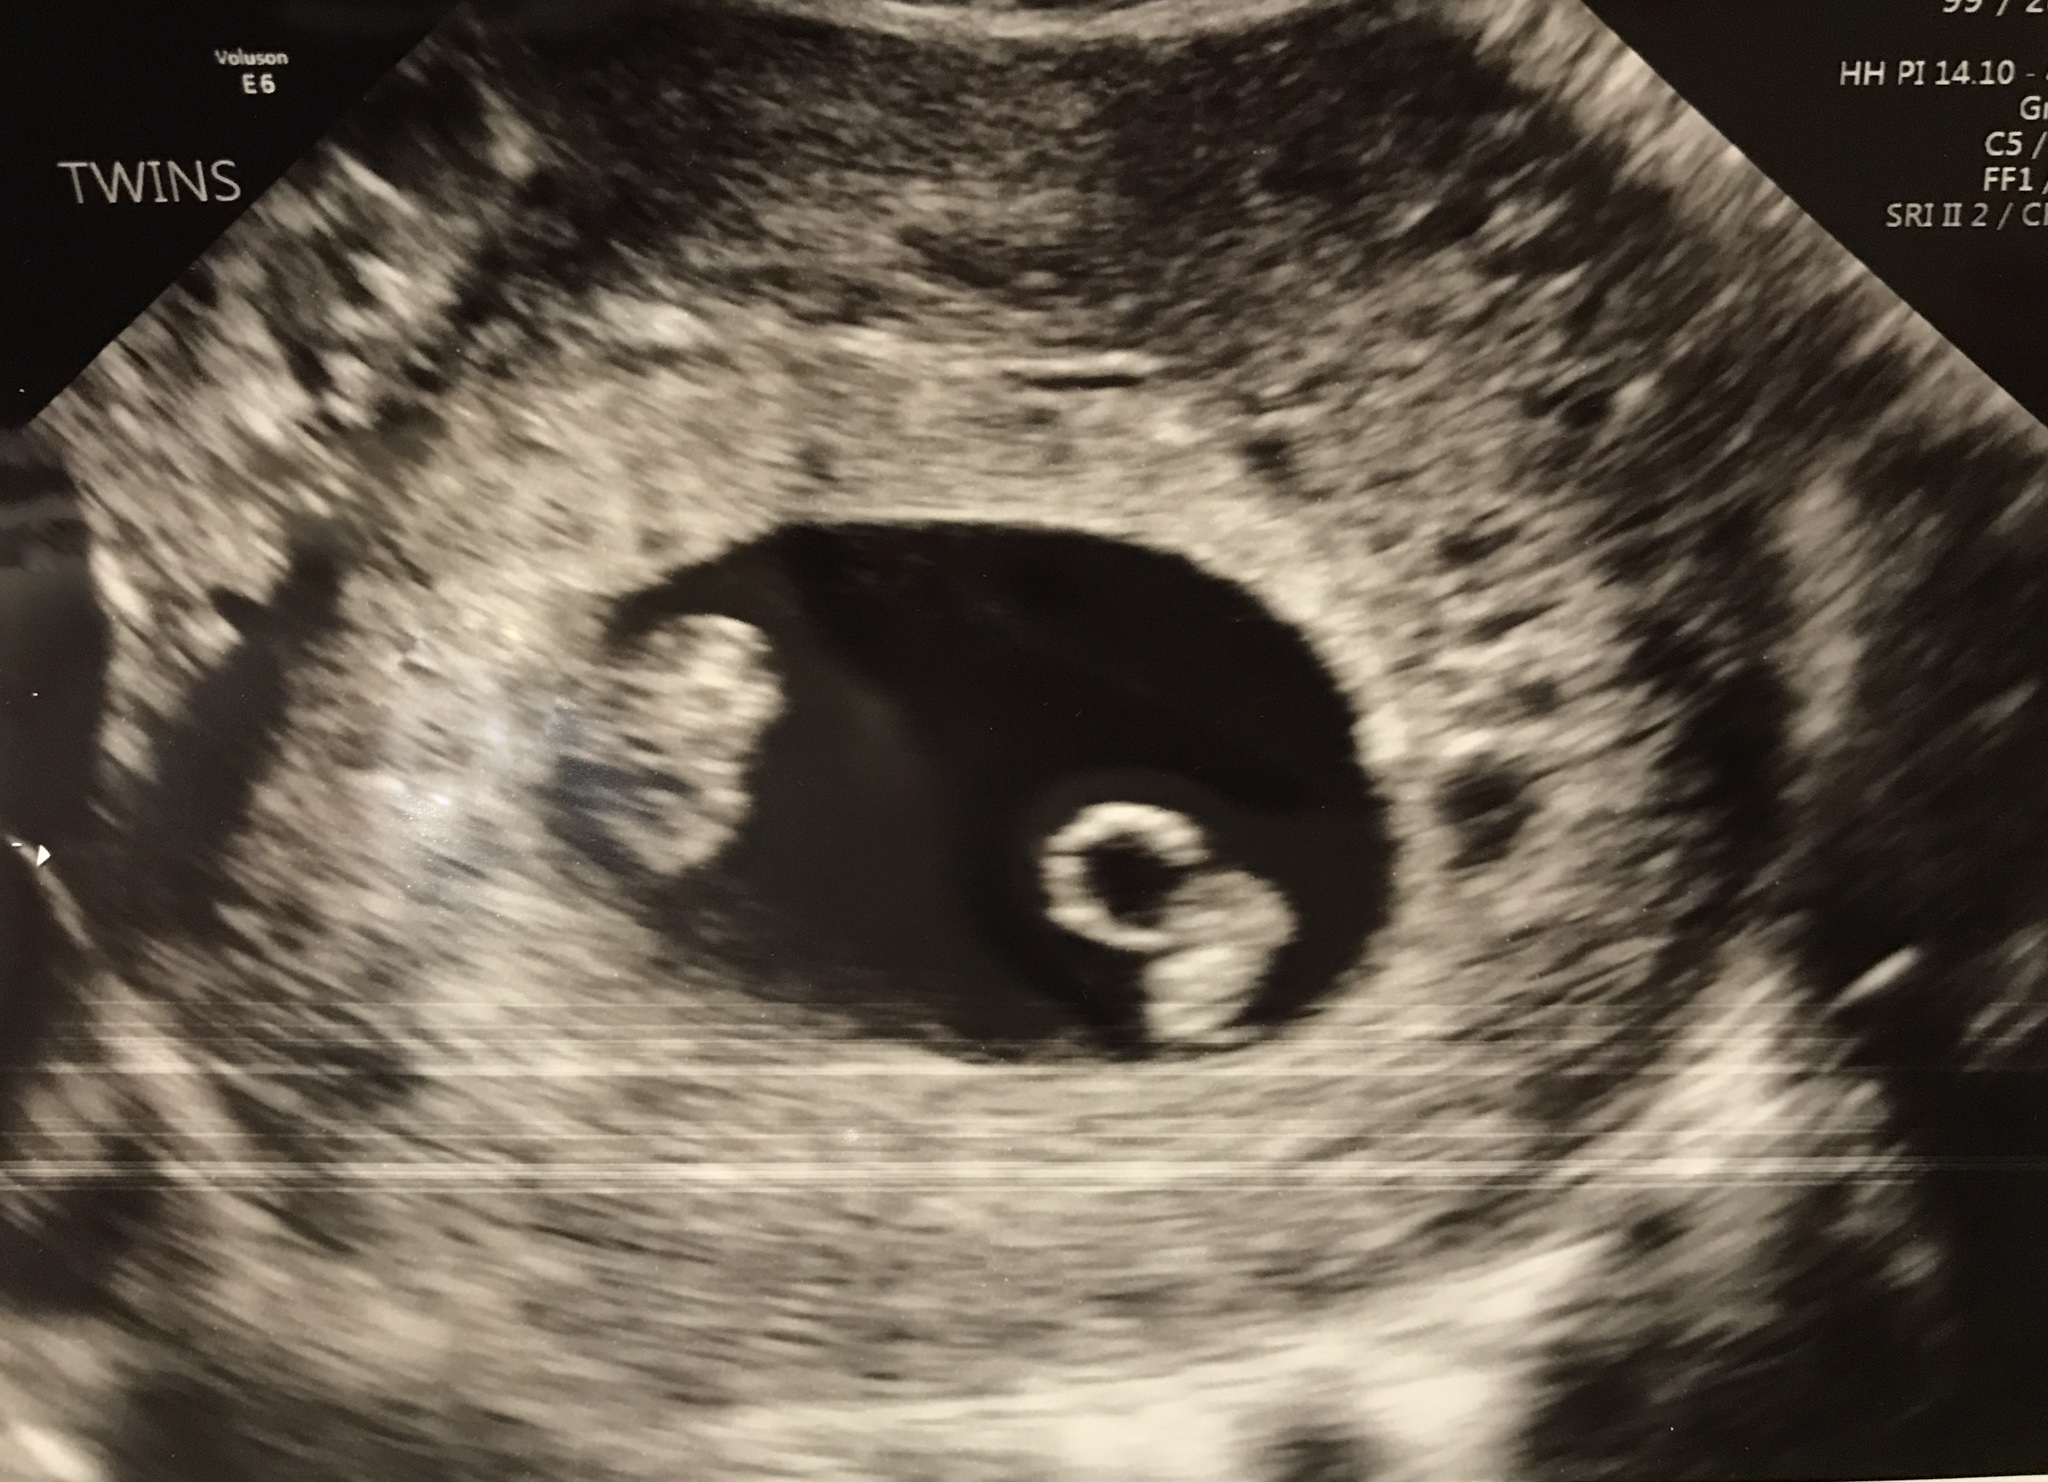

BUT THEN at that 6 week appointment, while my husband and I were waiting and looking at that little screen, our tech asked us “are you ready for this?” and I just KNEW what she was going to say. I swear I just KNEW.

TWO BABIES. TWINS. YOU HAVE TWO BABIES IN THERE.

In that moment I knew it was meant to be, the universe, God, was somehow making up for the loss we went through. TWO BABIES. We left that appointment with a beautiful ultrasound photo of our two little beans and I realized…I was SO scared. How are we going to take care of two babies? Can we afford two babies? What about daycare, work? My brain was immediately going through the next few years of life, wondering how it would all work, question after question. No one had ever told me how much WORRY comes with motherhood. I’ll tell you now that the worry never ends.